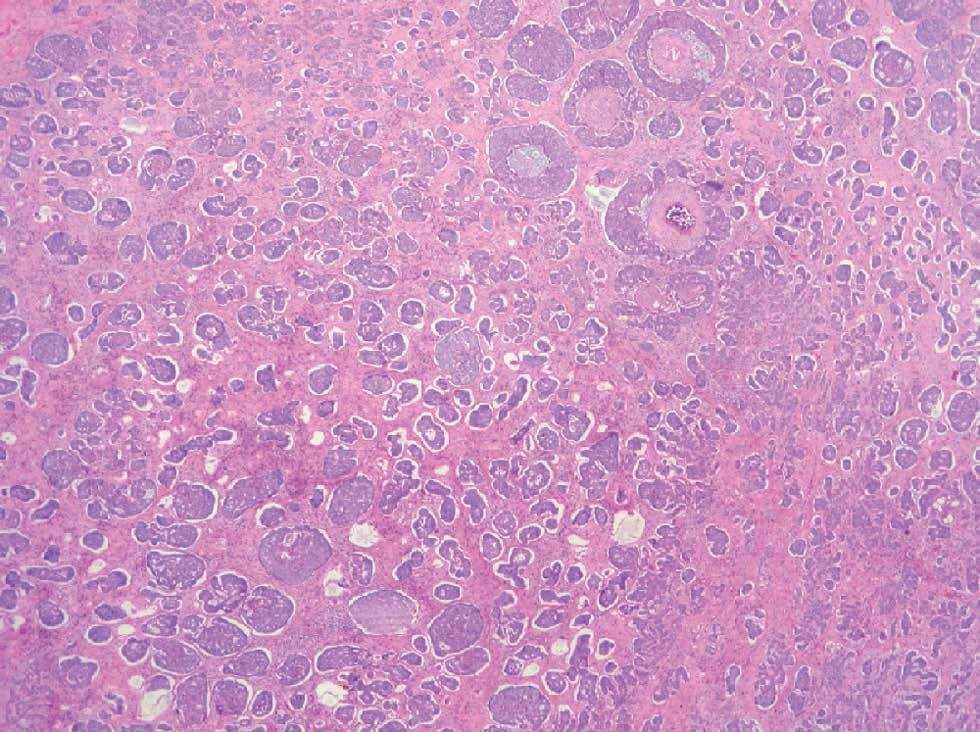

El estudio anatomopatológico revelaba una epidermis sin alteraciones destacables. Se observaba en toda la dermis y contactando con el tejido subcutáneo un tumor constituido por células germinativas foliculares que adoptaban varios patrones de crecimiento: en nódulos grandes, nódulos pequeños (fig. 2), cribiformes, racemiformes y retiformes (fig. 3). Los nódulos mostraban una parcial disposición periférica en empalizada, apreciándose en varios de ellos necrosis central y figuras de mitosis relativamente frecuentes. El estroma colágeno era denso con frecuentes fibrocitos, con zonas de aspecto mixoide, sobre todo en relación con las zonas de crecimiento retiforme, a las que también se asociaban un mayor número de quistes infundibulares. Se observaba también un componente de células claras, asociado al patrón histológico de nódulos grandes, con positividad para la tinción con ácido periódico de Schiff (fig. 4).

Fig. 2.--Patrón en nódulos pequeños (hematoxilina-eosina).